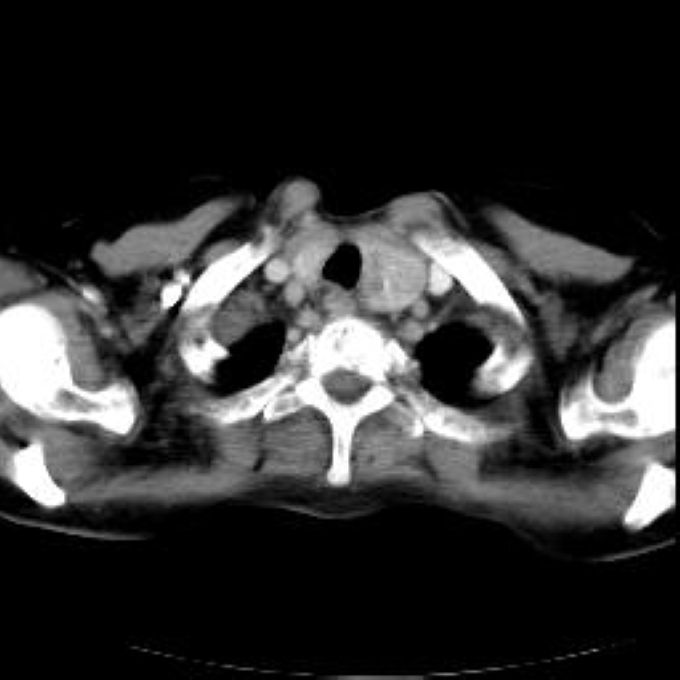

Arteria lusoria.

56 year old patient with dyspagia. A tumor of soft tissue was described in upper mediastinum on plain X-ray of the thorax. What is this mass in the upper mediastinum?